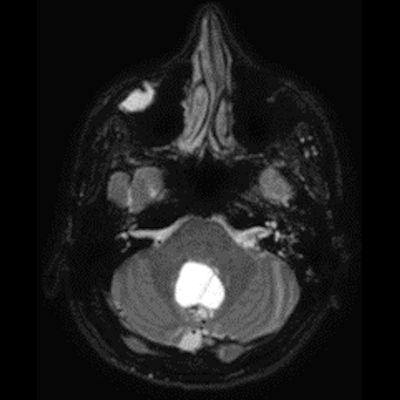

- A) Beyin BT incelemede; posterior fossada hipodens, düzgün sınırlı kistle beraber (oklar), posteriorunda 8 mm boyutunda, iyi sınırlı, kontrastsız BT’de parankim ile izodens, postkontrast görüntülerde yoğun kontrast tutulumu gösteren mural nodül komponenti (oklar) gözlenmektedir.

- B) Beyin MRG incelemesinde; 4. ventriküle bası etkisi oluşturan yaklaşık 3.5 cm boyutta, T2A hiperintens T1A hipointens kistik komponent (oklar) ve posteriorunda T1 ve T2A serilerde parankim ile izointens, içerisinde flow void alanların (oklar) izlendiği, post kontrast görüntülerde yoğun kontrast tutulumu gösteren mural nodül (oklar) barındıran düzgün sınırlı lezyon izlenmektedir.

- Kistik komponent: T1A hipointens, T2A hiperintens

- Mural nodül: T1A izo-hipointens, T2A orta derecede hiperintens olabilir.

- Kontrastlı incelemelerde mural nodül belirgin ve yoğun kontrast tutulumu gösterir. Ancak kist duvarında genellikle kontrastlanma beklenmez.

- T1 ve T2A görüntülerde flow voidler sıktır.